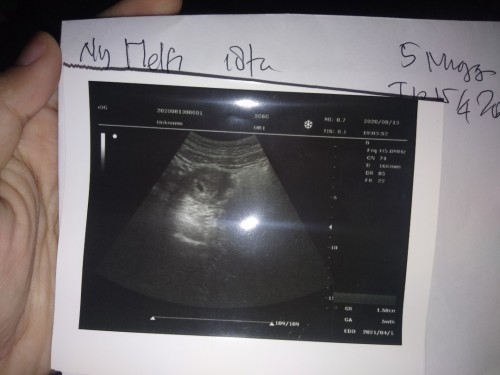

Ada yg pernah gak? Klo dihitung dri hpht misalkan usia kehamilannya 5minggu 6hari tpi pas usg masih 5minggu 4 hari kayak gtu,beda duahari? Ini hasil usg aku brusan, kata dokternya sih bru kantong doang yg kelihatan,jdi dsuruh blik lagi 2 minggu kemudian, ada yg pernah usg 5 minggu dh kelihatan janinnya?

Bun USG perut atau transvaginal ,ko agak beda ya hasil USG nya aku USG hamil 5 week